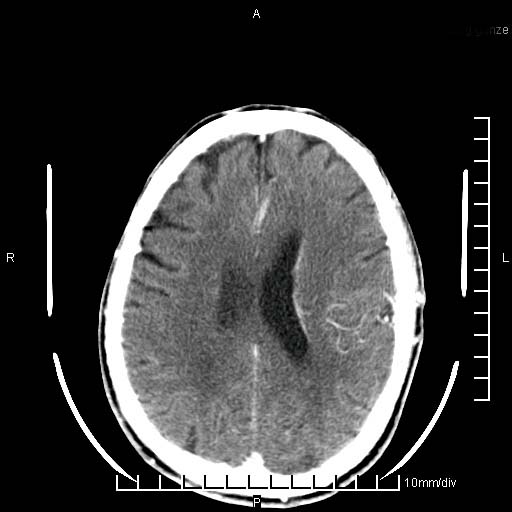

临床以双下肢浮肿,疼痛收治,无明显神经系统症状,既往无梗塞,出血病史。左颞叶见低密度灶,考虑什么?

考虑左侧颞叶脑软化灶。

无强化 无占位 软化灶吧

无强化、 无占位、局部脑沟增宽, 软化灶吧。